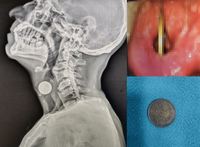

¼ú ¸Ô°í ÇÑ Àå³À¦ ¸ñ¿¡ ¡®À̰͡¯ ¹ÚÇô ¸ñ¼Ò¸® ¾È ³ª..

°úÀ½ ÈÄ »ïŲ µ¿ÀüÀÌ Èĵο¡ °É¸° 50´ë ³²¼ºÀÇ »ç·Ê°¡ º¸°íµÆ´Ù.Àεµ ¸¶¿ï¶ó³ª¾ÆÀÚµåÀÇ´ë À̺ñÀÎÈİú¡¤µÎ°æºÎ¿Ü°ú ÀÇ·áÁø¿¡ µû¸£¸é 51¼¼ ³²¼ºÀÌ 4ÀÏ µ¿¾È Áö¼ÓµÈ ½® ¸ñ¼Ò¸® Áõ»óÀ» È£¼ÒÇÏ¸ç º´¿øÀ» ã¾Ò´Ù. ´ç½Ã ±×¿¡..